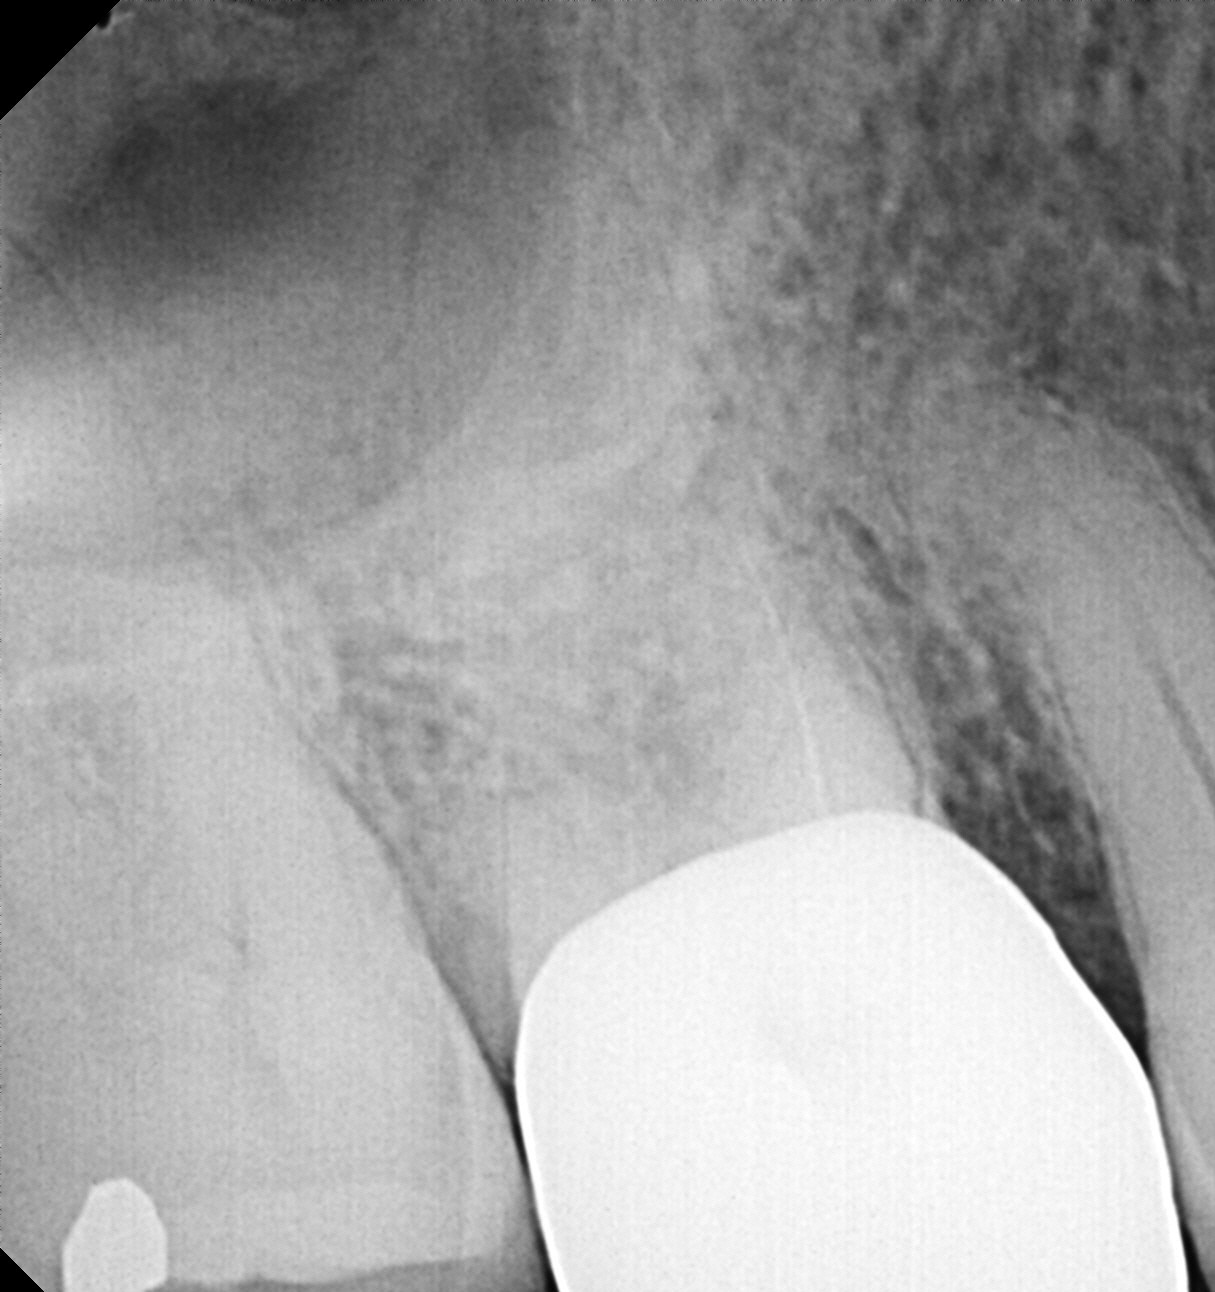

Patient was referred for a Root Canal Treatment #3. Diagnosis: PN/SAP. Access prep completed. Orifice opening completed with ProTaper Universal SX. While scouting for WL, a .10 hand file separated in the MB1 canal. The tip was near the junction with MB2, and the separation occurred near the orifice. Sponge and Cavit placed and new radiograph made. Ultrasonics used to trough around file mostly lingual to the instrument, using the MB2 canal as a guide until the MB2 canal joined the MB1. Doing this, tooth structure palatal to the file was removed and very little tooth structure along the outer edges of the canal system required removal. During this process, about 3mm of the coronal portion of the file broke and was removed. At this point, I switched to the TFRK ultrasonics and continued until 2-3mm of the file was exposed and there was some mobility present. EndoCowboy 0.12mm used to lasso the file. File removed in its entirety without complication. Case completed without further complication. No additional visit necessary. Post-op PA showed minimal loss of tooth structure required for file removal.